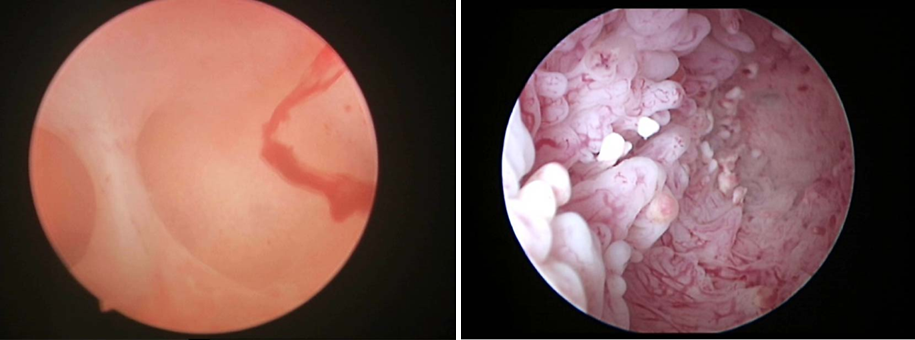

宫腔粘连 多发子宫内膜息肉

(4)其他检查:①基础体温测定:双相型体温变化提示排卵可能,但不能作为独立的诊断依据②宫腔镜、腹腔镜检查:适用于体格检查、超声检查和(或)输卵管通畅检查提示存在宫腔或盆腔异常的患者,可明确病变位置和程度,并进行相应的治狞疗。

2.子宫病变 对于子宫黏膜下肌瘤、较大的肌壁间肌瘤、子宫内膜息肉、宫腔粘连和纵隔子宫等,若显著影响宫腔形态,则建议手术治疗;子宫明显增大的子宫腺肌症患者,可先行GnRH-a治疗2~3个周期,待子官体积缩至理想范围再行辅助生殖技术助孕治疗。